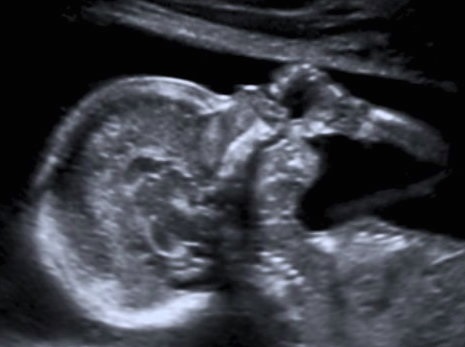

![]() Hoy recurrimos más a la psicología para entender el por qué de nuestras conductas, cómo nos relacionamos con los demás y para quienes tenemos hijos, sus comportamientos, más aún cuando son pequeños. Si tienes un hijo pequeño; lo más probable es que una de las acciones que se repita a menudo es que se chupe su dedo, y para esto también la piscología nos da una explicación. Primero que nada debemos saber que muchos bebés y niños se chupan los dedos pulgares incluso cuando todavía están en el vientre materno. Es fisiológico y es un signo de madurez de su desarrollo psicomotor que puede considerarse normal hasta cierta edad. A partir de la decimosegunda semana de gestación, el bebé empieza a realizar este gesto y este hecho se ha podido confirmar cuando se realiza una ecografía durante el control prenatal. Cuando el bebé nace y activa este reflejo, se pueden producir dos tipos de succión: Tipos de succión